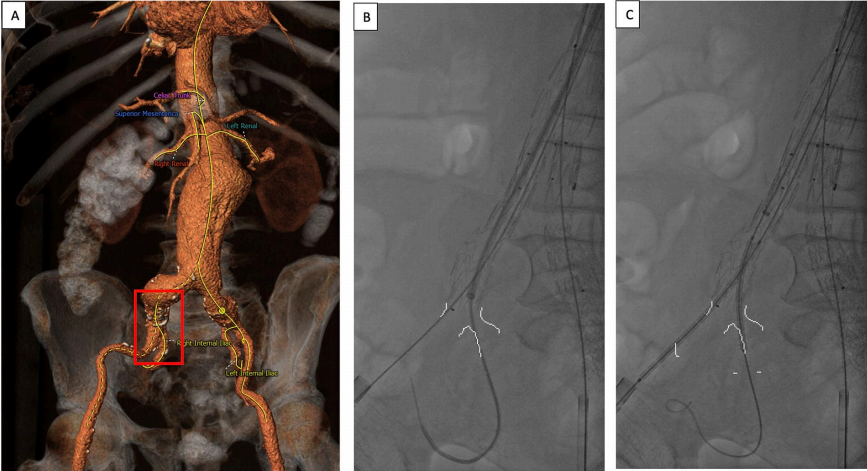

1.在完成EVAR/BEVAR(腹主动脉瘤腔内修复/分支技术腔内修复腹主动脉瘤)或髂支展开后,髂支的远端部分展开在髂内外分叉部上方1至1.5厘米处(图1A和B)。腋动脉入路放置第一个球扩覆膜支架至髂内动脉:将7Fr或8Fr亲水涂层鞘管(通常长度为80毫米)沿导丝推进至降主动脉,并延伸至髂动脉分叉部位。在主动脉弓成角和BEVAR病例中,可能预先置入更大规格的12Fr鞘管,随后沿亲水导丝送入5Fr椎管至IIA。

2. 股动脉入路放置第二个球扩覆膜支架至髂外动脉:两个支架对吻,放置在髂支内至少2至4厘米处(图1C)。

图1